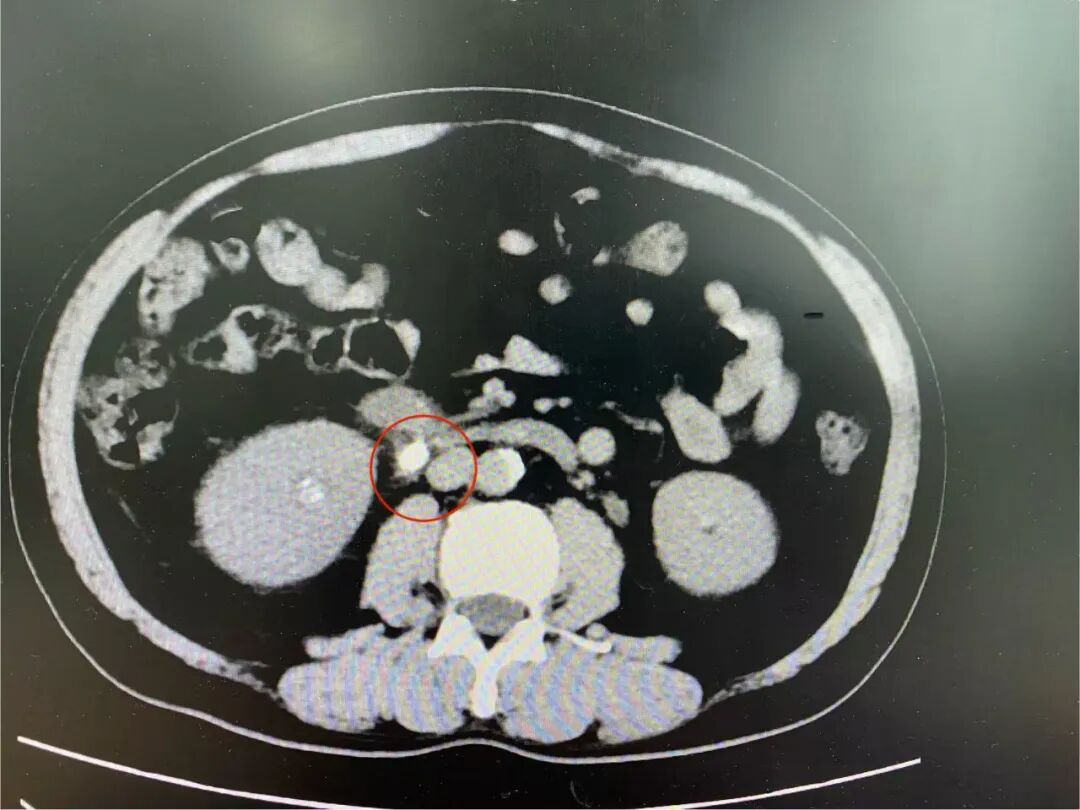

经泌尿系CT等检查,张先生被确诊为输尿管结石。

↑标红处为结石

检查结果显示,张先生血钙指标为3.39mmol/L,远超正常范围(2.11-2.52mmol/L),这一异常引起了泌尿外科医生的高度警惕。